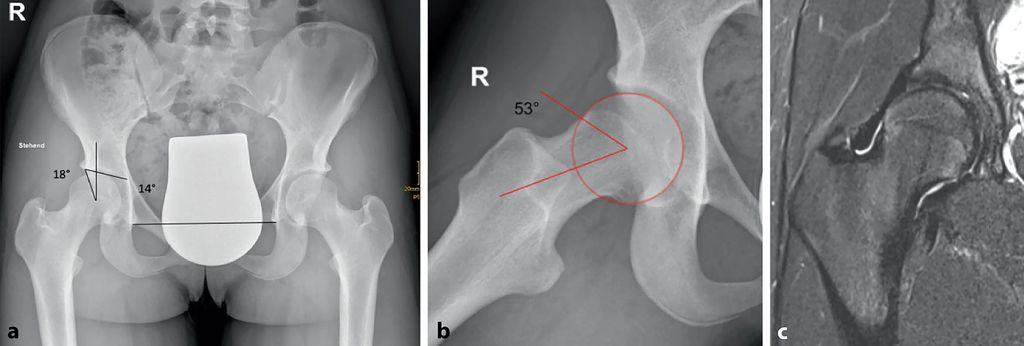

Abb. 1: 14-jährige aktive Balletttänzerin mit Schmerzen bei starker Abduktion und Außenrotation. Im Projektionsröntgen ap (a) zeigt sich eine Grenzdysplasie (LCE-Winkel 18°, Tragflächenwinkel 14°), in der Dunn-View (b) ein verminderter femoraler Offset mit einem Alpha-Winkel von 53,4°. Die MRT (c) zeigt ein geringgradiges Knochenmarködem am Kopf-Schenkelhals-Übergang als Zeichen des FAI (aus Chiari et al. 2022)5